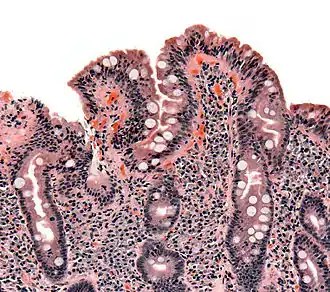

![]() Biopsia de intestino delgado en la que se aprecia atrofia de las vellosidades intestinales, hiperplasia de las criptas y linfocitosis intraepitelial. | ||

A diferencia de los criterios habitualmente utilizados por los expertos, las lesiones que la enfermedad celiaca provoca en el intestino delgado se limitan habitualmente a la presencia de una inflamación crónica de la mucosa duodenal, constituida principalmente por linfocitos, sin atrofia de las vellosides intestinales, especialmente en los niños mayores de dos años y los adultos. Actualmente, la presencia de atrofia de las vellosidades se considera un hallazgo menos frecuente.[19][50][51][52][40][53] También en contraposición de los criterios habitualmente empleados en la práctica clínica diaria, actualmente está reconocido que la celiaquía cursa frecuentemente con serología negativa (ausencia de anticuerpos específicos en sangre), especialmente la anti-transglutaminasa.[19][50][40][54][55][56][57] Esto se debe a que la anti-transglutaminasa se produce en la mucosa del intestino y con frecuencia, permanece depositada en ella sin pasar a la sangre.[20] [26][58] [59] Su evaluación en las biopsias duodenales es un nuevo método diagnóstico, que puede ayudar a detectar la enfermedad, pero es una técnica compleja, engorrosa y cara, por lo que su empleo no está generalizado en la práctica clínica habitual.[40][60][61] Esta prueba ha sido incluida en 2018 en España, como parte del nuevo protocolo para el diagnóstico precoz de la enfermedad celíaca.[62]

Las lesiones que la celiaquía provoca en el intestino delgado de un celíaco no se limitan a la presencia de atrofia de las vellosidades intestinales, sino que con frecuencia consisten en cambios mínimos, con inflamación leve o moderada, especialmente en los niños mayores de dos años y los adultos.[19][50][51][52] [40]

El contacto del intestino con el gluten conduce a la aparición de un daño en la mucosa del intestino delgado que no se limita, como tradicionalmente se pensaba, a la atrofia de las vellosidades intestinales, sino que incluye una serie de cambios inflamatorios que son mucho más frecuentes que aquella. Las lesiones abarcan desde casos en los que únicamente se aprecia un aumento de la población de linfocitos intraepiteliales (enteritis linfocítica) hasta formas avanzadas de atrofia vellositaria.[19][50] Cualquiera de estas lesiones, incluso las formas más leves, puede cursar con diversos estados carenciales, incluyendo anemia, osteopenia u osteoporosis, y un amplio abanico de síntomas digestivos y extradigestivos;[19][50] y presentan riesgo de complicaciones importantes a largo plazo si permanecen sin diagnosticar ni tratar, incluyendo un aumento moderado de la mortalidad.[156]

- Lesión tipo Marsh 1. Se observan 20 o 25 linfocitos intraepiteliales (depende de la técnica de tinción) por cada 100 enterocitos. Se expresa mediante porcentaje. Es decir, se considera Marsh 1 cuando la infiltración linfocitaria (LIES) es superior al 20 % o 25 %. Esta enteritis linfocítica es el hallazgo histológico más habitual en la enfermedad celíaca del adulto y niño mayor de 2 años.

- Lesión tipo Marsh 2. Se observa el patrón anterior además de hiperplasia de criptas (están en la base de las vellosidades).

- Lesión tipo Marsh 3. Se observa el patrón anterior y además existe acortamiento (atrofia) de vellosidades. Se subdivide en: